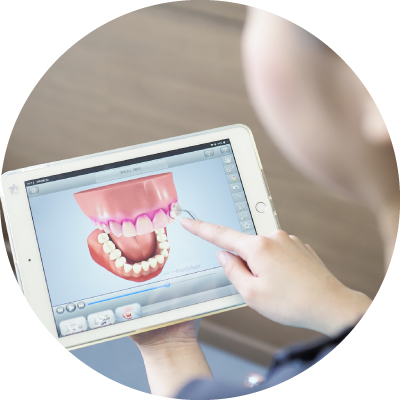

初診基礎検査

患者さんの現在の状況を把握するために、3つの「基礎検査」を行っています。検査内容は①レントゲン撮影、② 口腔カメラ撮影、③歯周病検査です。また、痛みや不具合がある場合は、それらを軽減するための「応急処置」も行います。